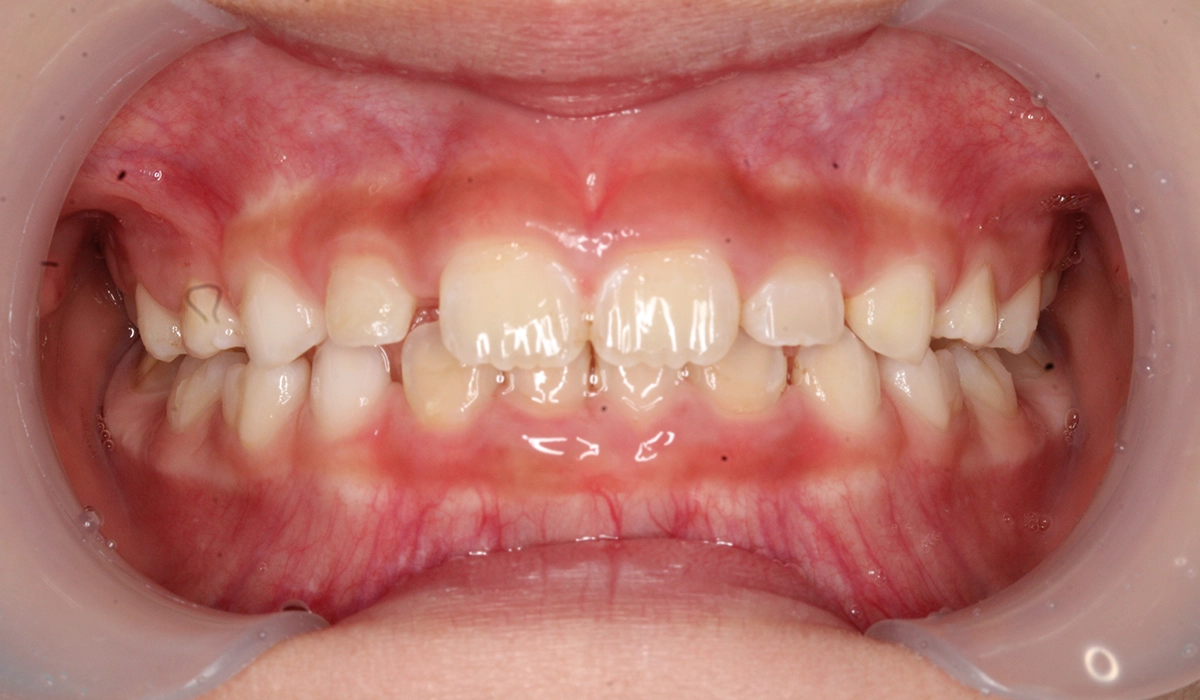

術前:正面

術後:正面